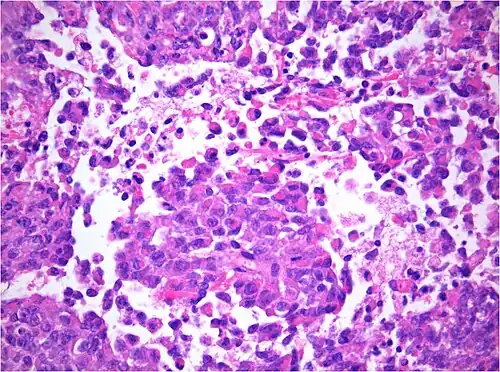

AT/RT and rhabdoid tumor share the term "rhabdoid" because under a microscope, both tumors resemble rhabdomyosarcoma.

AT/RT Histology with numerous rhabdoid tumor cells -

Rhabdoid Tumor Cell - 400X Magnification

The tumor histopathology is jumbled small and large cells. The tissue of this tumor contains many different types of cells including the rhabdoid cells, large spindled cells, epithelial and mesenchymal cells, and areas resembling primitive neuroectodermal tumor (PNET). As much as 70% of the tumor may be made up of PNET-like cells. Ultrastructure characteristic whorls of intermediate filaments are seen in the rhabdoid tumors (as with rhabdoid tumors in any area of the body). Ho and associates found sickle-shaped embracing cells, previously unreported, in all of 11 cases of AT/RT.[24]